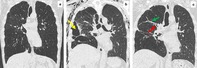

The use of endobronchial valves (EBV) is a recommended treatment for persistent air leak (PAL) and endoscopic lung volume reduction (ELVR) in selected patients with severe emphysema and absence of collateral ventilation. We report the case of a 52-year-old man who was scheduled for a bilateral sequential lung transplantation, converted to a left single lung transplantation (SLTx) after failure to remove the right lung due to prior thoracic surgery. The post-operative course was complicated by a PAL on the right non-transplanted side, unresponsive to prolonged drainage. Placement of EBV in the right upper and middle lobes, following collateral ventilation evaluation with the Chartis system, resulted in the resolution of the air leak and a concomitant lung volume reduction. Based on a literature review regarding ELVR in single-lung transplanted recipients, we suggest that ELVR with EBV could be a therapeutic option with an acceptable safety profile in this unique population.

Abstract Image